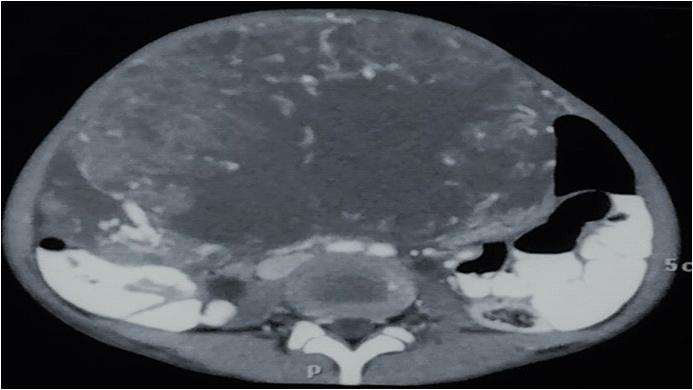

CT scan and/or MRI abdomen pelvis : CT Scan and/ or MRI abdomen pelvis was performed in 16 cases, both were accurately demonstrated the anatomical relationship of associated intra pelvic organs with surrounding fat and pelvic lymph nodes. CT Scan and/ or MRI abdomen pelvis clearly depicted prostatic utricle cysts in 3/3(100%) cases, intraprostatic abscess cavities in 2/2 (100%) cases, seminal vesicle cysts 2/ 2 (100%) and cystic connective tissue masses in 4/4 (100%). CT scan abdomen pelvis accurately demonstrated retro-vesical connective tissue solid masses in three cases. CT scan and/or MRI abdomen pelvis failed to differentiate accurate diagnosis in two cases (ejaculatory duct cyst and mullerian duct cyst with cystadenoma). However, MRI failed to differentiate between teratoma and haematoma. FNAC accurately demonstrates diagnosis in two cases of intraprostatic abscess (Fig 6).